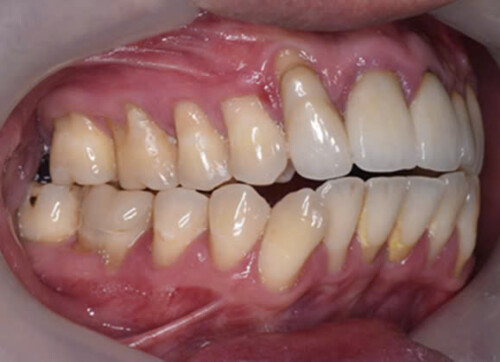

Hình 2: Hình ảnh tiêu cổ răng, tụt lợi do sang chấn khớp cắn ở bệnh nhân nam giới độ tuổi 30. Bệnh nhân than phiền ê buốt răng và tình trạng bong mối hàn thường xuyên.